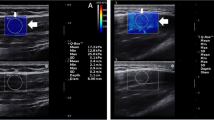

The TLF shear modulus was measured at the third and fourth lumbar vertebra levels (L3 and L4).The location of the L4 spinous process was identified by a body surface marker and reconfirmed by B-mode ultrasound. Then, the position of the L3 spines is determined by B-mode ultrasound. The longitudinal center of the probe at horizontally 2 cm from the right side of the L2–3 and the L3–4 midline (Fig. 1)5,15,16. These gauge points were marked with an oil-based pen. The marker of each experiment was cleaned at the end of the experiment.

All subjects performed experiments in a given posture: sitting, sitting-forward 60° (Fig. 1). In all postures, subjects are required to keep their heads in a neutral posturewith their upper limbs at their sides. In sitting posture, the subjects are required to keep their feet shoulder-width apart and both feet flat on the floor. Their legs are perpendicular to the ground, and their knees bent at 90°.We used a self-made sloping panel to keep the subjects' upper body at 0° and 60° of forward tilt.

To ensure that the muscles and fascia are at rest, the subjects were allowed to have a 5 min rest before testing. Then, the subjects were placed at appropriate posture, and ultrasonic gel was applied to the skin around the marked location. Under the B-mode image, the probe was placed perpendicular to the skin and slightly adjusted parallel to the upper tendon muscle fibers to obtain a clear image. Once the probe orientation was aligned with the direction of the muscle fibers, we switched to E mode to quantify the shear modulus of the upper TLF (Fig. 2). The size of the region of interest (ROIs) is set to match the thickness of the TLF shallow (a variable range is chosen to achieve a larger area and to keep the border of the ROIs at a certain distance from the upper subcutaneous tissue and the lower muscles17).Three measurements were taken for each measurement point, and the measurements were averaged. In addition, to avoid the influence of abdominal fluctuation caused by breathing, we specifically save the image at the end of expiration to ensure the consistency of test results.